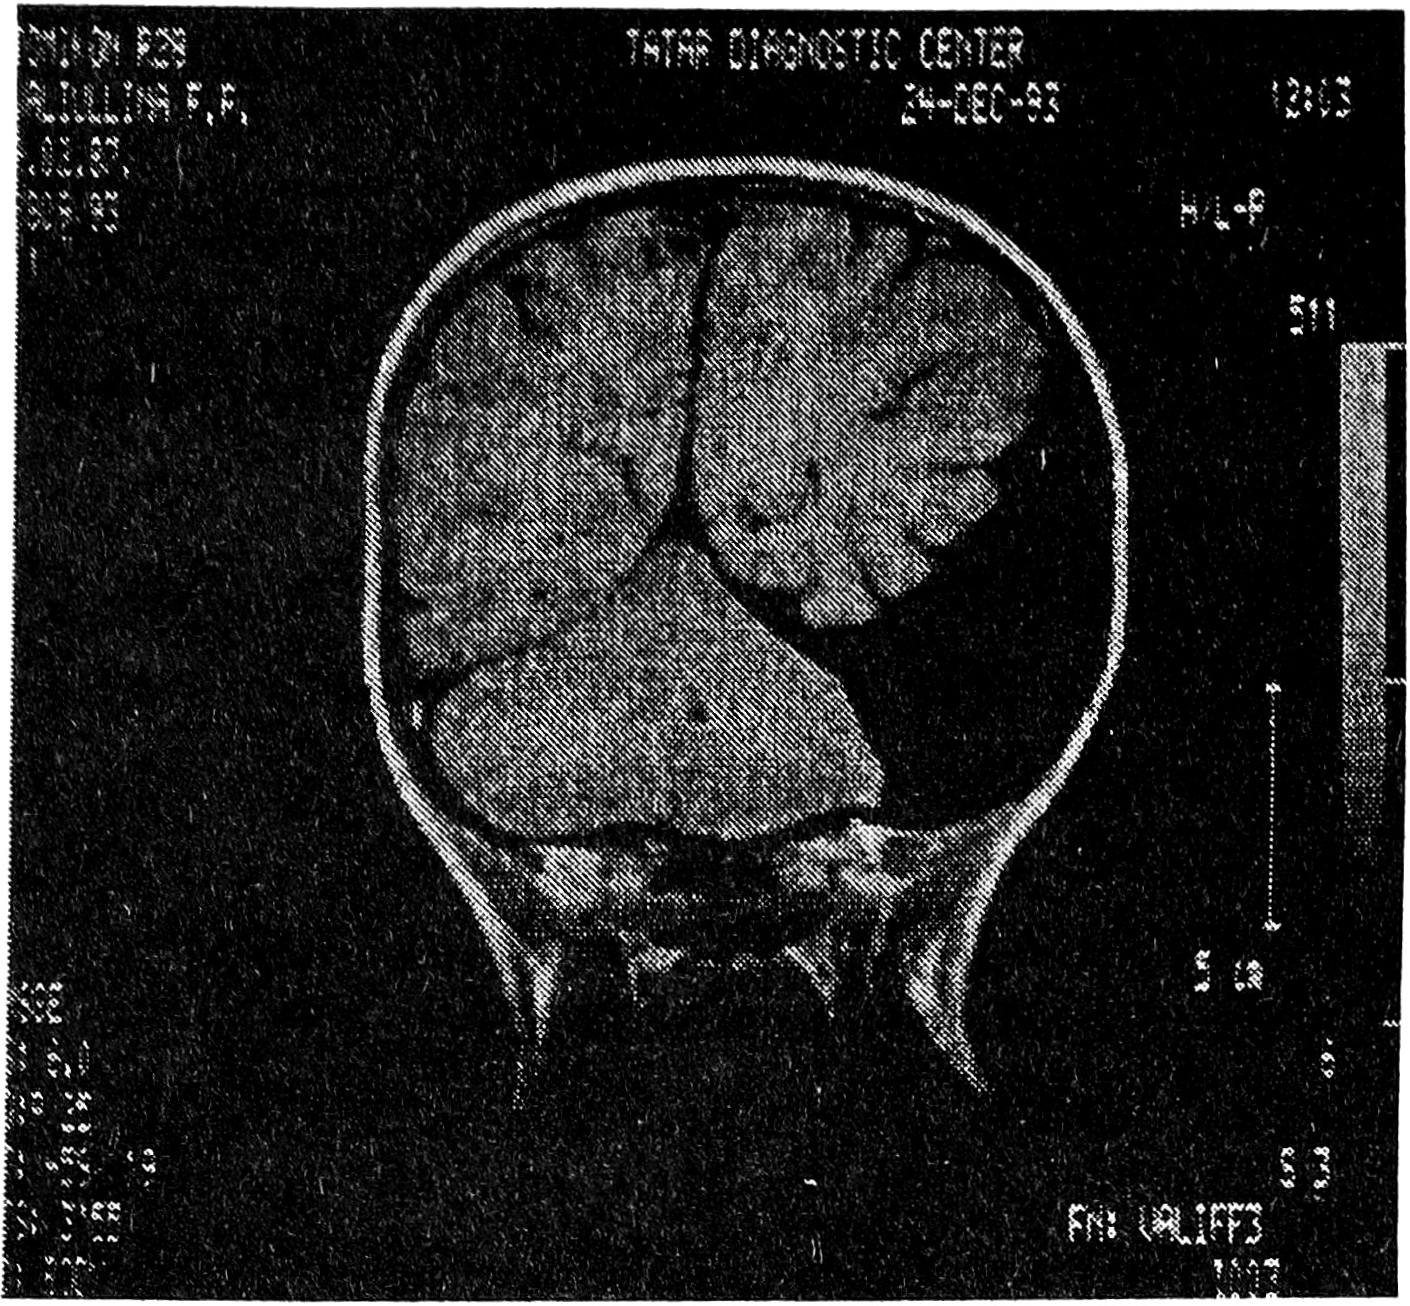

Рис. 1. ЯMP-томограмма арахноидальной кисты над правым полушарием головного мозга.

Клинико-неврологическая диагностика ВАК крайне затруднительна. Большинство обследованных больных на втяжении длительного отрезка времени лечились по поводу вегетососудистых дисфункций, гипертензионно-гидроцефальных синдромов неясной этиологии, стойких остаточных явлений после перенесенных нейроинфекций, травматической энцефалопатии. Псевдотуморозный тип развития заболевания (прогредиентный или прогредиентно-ремиттирующий), сочетание гидроцефально-гипертензионного синдрома с медленно прогрессирующей или стабильно существующей очаговой симптоматикой на фоне краниографически верифицируемых гидроцефальных изменений в виде истончения кости, ее дуальных деформаций, углублений основания черепа настораживают в отношении возможности ВАК и определяют необходимость использования визуальных методов обследования мозга [3, 4]. Наиболее убедительные данные могут быть получены в результате выполнения ЯМР- и КТ-томографий, причем первый из упомянутых методов является наиболее информативным. Возможность получения ЯМР-томограмм практически в любой из желаемых плоскостей существенно расширяет разрешающую способность метода и позволяет с его помощью дифференцировать ВАК и кисты другой природы.